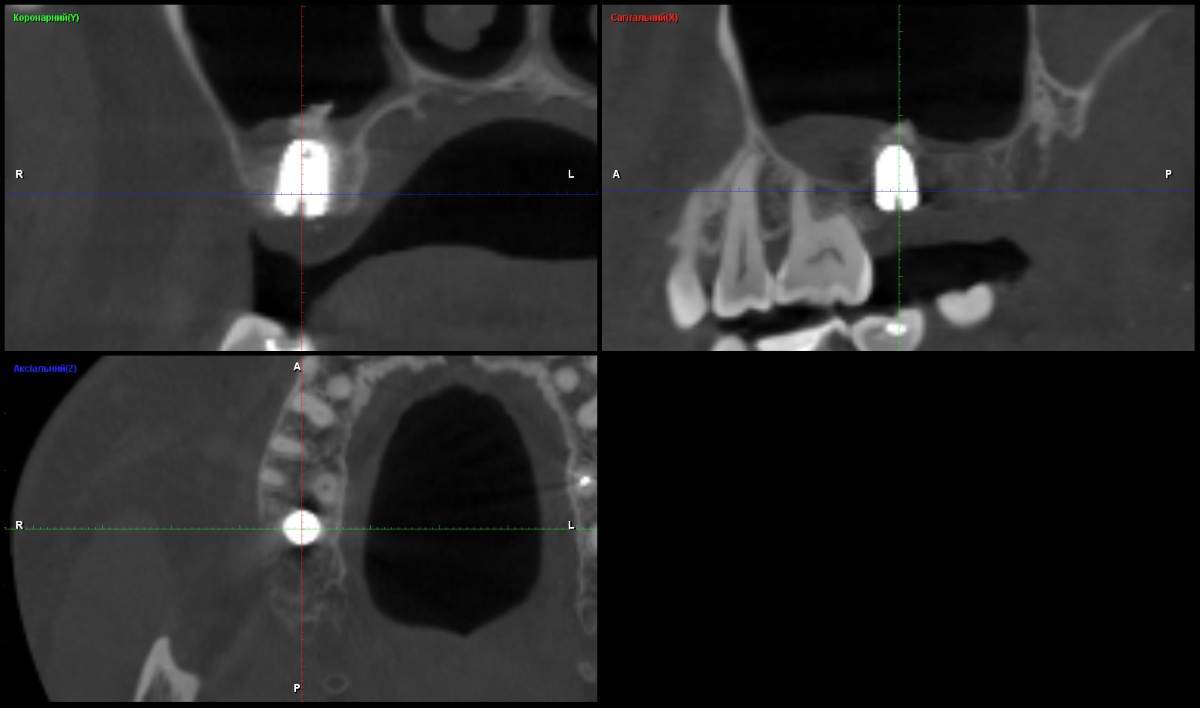

pmu15 Опубликовано 22 сентября, 2025 Поделиться Опубликовано 22 сентября, 2025 (изменено) Прошу посмотреть КТ, сделанное через месяц после закрытого синус-лифтинга с установкой импланта (7-й зуб справа сверху). Меня беспокоит то, что верхушка импланта, по-видимому, заходит в гайморову пазуху (вместе с костным материалом?). После операции в течение недели отмечалось: 1. небольшое кровотечение в носоглотке, 2. выход «крупинок» белого цвета, похожих на песчинки (примерно 15 штук, откашлял). Возможно, это был костный материал. Вопросы: 1. Насколько критично проникновение импланта (и костного материала) в пазуху? 2. Опасны ли описанные симптомы (кровь и «крупинки») или это вариант нормы после операции? 3. Нужно ли в этой ситуации дополнительное лечение или наблюдение? Ссылка на КТ файл DICOM https://disk.yandex.ru/d/jznDAo6CI7458g Изменено 22 сентября, 2025 пользователем pmu15 Добавил КТ Ссылка на комментарий

pmu15 Опубликовано 23 сентября, 2025 Автор Поделиться Опубликовано 23 сентября, 2025 Здравствуйте! Спасибо за ответ Да, мне объяснили, что синус-лифтинг проводится для увеличения объёма кости и надёжной фиксации импланта. Хотел уточнить, на КТ заметно острое образование у верхушки импланта, выходящее в пазуху. Это вариант нормы? Ссылка на комментарий

Женька Опубликовано 23 сентября, 2025 Поделиться Опубликовано 23 сентября, 2025 @pmu15 Я же уже ответил) проблем на снимке не вижу, не переживайте. Это, очевидно, кусочек костной ткани которую выбили и приподняли вместе со слизистой пазухи . Ссылка на комментарий